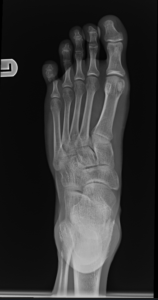

- Foot Fractures.